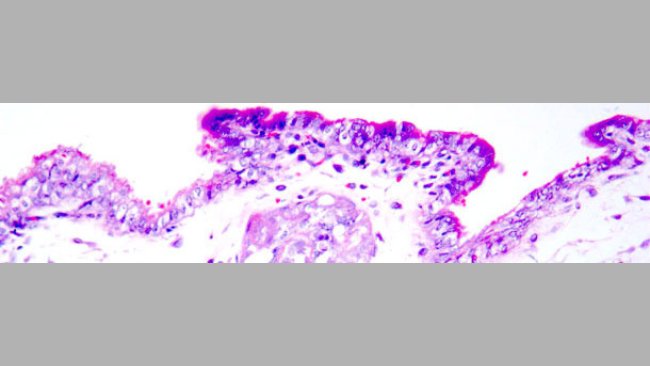

Cas clinique: Problèmes respiratoires et de reproduction dans un élevage de porcs

Après l’évaluation clinique et sérologique, on décide de vacciner contre le SDRP, ce qui permet une amélioration sanitaire de l’élevage. Quelques mois après une toux sévère apparait en engraissement puis en post-sevrage et aussi chez les truies.